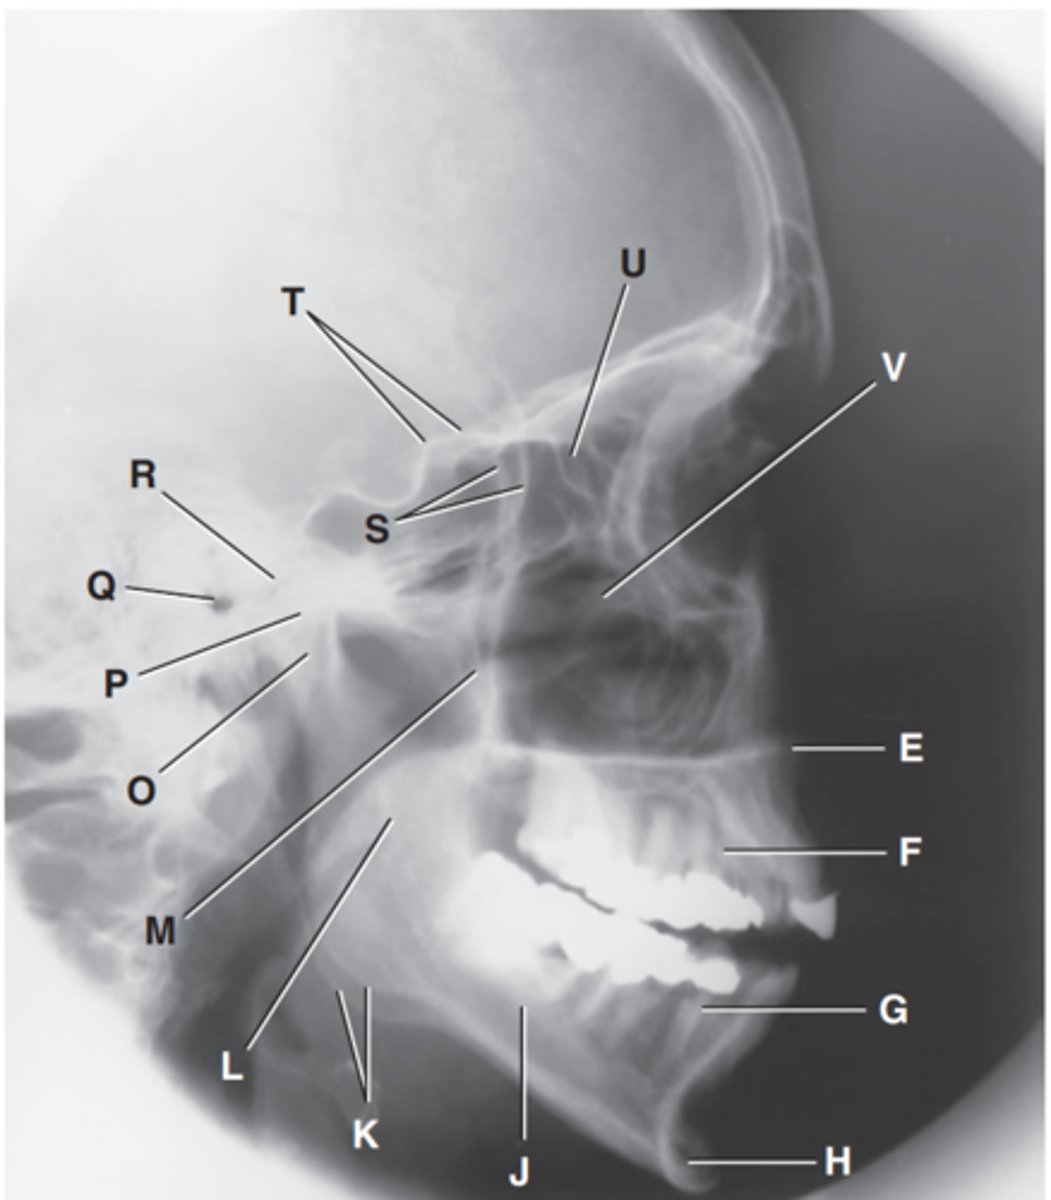

Zygomatic arch

Label A

Right zygomatic bone

Label B

Right nasal bone

Label C

Frontal process of right maxilla

Label D

Anterior nasal spine

Label E

Alveolar process of maxilla

Label F

Alveolar process of mandible

Label G

Mentum or mental protuberance

Label H

Mental foramen

Label I

Body of mandible

Label J

Angle (gonion)

Label K

Ramus of mandible

Label L

Coronoid process

Label M

Mandibular notch

Label N

Neck of mandibular condyle

Label o

Condyle or head of mandible

Label P

EAM

Label Q

TM fossa of temporal bone

Label R

Greater wings of sphenoid

Label S

Lesser wings of sphenoid with anterior clinoid processes

Label T

Ethmoid sinuses between orbits

Label U

Body of maxilla containing maxillary sunuses

Label V